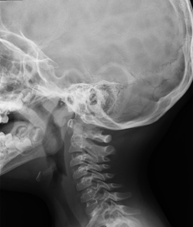

- Cervical spine X-ray

This technique uses X-ray rendered imaging for examining the cervical spine. Indicated for: trauma, cervical pain.

Técnica mediante la cual, utilizando rayos X, se obtienen imágenes de la columna cervical para su estudio. Indicaciones: traumatismo, contractura cervical, dolor articular. - RX Huesos propios nasales